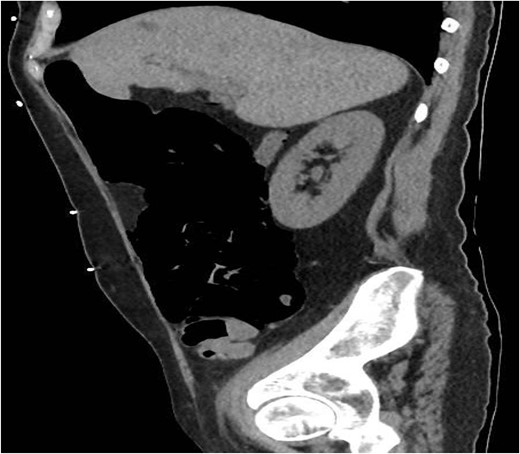

A 49-year-old female with a background of stage IV diffuse large B-cell lymphoma and subsequent graft-versus-host disease from a bone marrow transplant presented to a rural hospital in New South Wales, Australia with 12-h history of painless per rectal bleeding and fever. On examination she had a soft, but distended abdomen. Laboratory investigations revealed thrombocytopenia and hypokalaemia. Computed tomography of the abdomen and pelvis had a bizarre appearance due to pneumatosis cystoides coli extending from the ileocaecal junction to the mid-transverse colon. Given her benign abdominal examination, her management was initially supportive with intravenous antibiotics, intravenous fluid resuscitation and correction of electrolyte abnormalities.

A 49-year-old female with a background of stage IV diffuse large B-cell lymphoma and subsequent chronic graft-versus-host disease (cGVHD) from a bone marrow transplant presented to a rural referral hospital in New South Wales with a 12-h history of painless per rectal bleeding and fever. She had undergone her last cycle of chemotherapy 12 months prior and her cGVHD was being treated with dexamethasone mouthwash, oral cyclosporine and an infusion of rituximab, administered the day prior to this presentation. On examination she had a soft, but distended abdomen. Laboratory investigations revealed thrombocytopenia and hypokalaemia. Computed tomography (CT) of the abdomen and pelvis had a bizarre appearance due to pneumatosis cystoides coli extending from the ileocaecal junction to the mid-transverse colon (Figs 1–3). A chest X-ray was also taken, which shows evidence transmural air within the ascending colon, including the hepatic junction (Fig. 4). Given her benign abdominal examination, her management was initially supportive with intravenous antibiotics, intravenous fluid resuscitation and correction of electrolyte abnormalities. She was subsequently transferred to a metropolitan tertiary hospital, under her usual treating haematologist with consultation by the colorectal surgical team. She recovered and did not require any acute surgical intervention for pneumatosis cystoides coli.